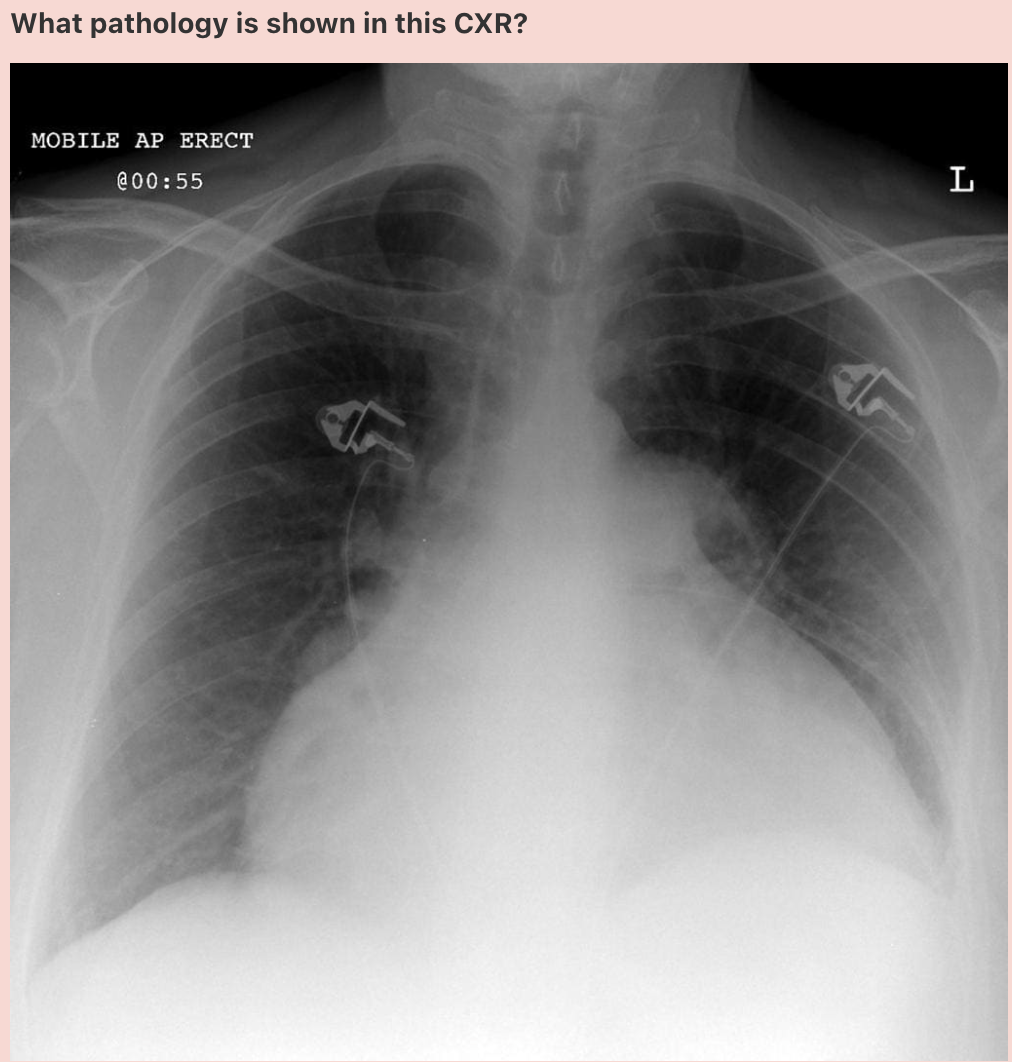

What pathology is shown in this chest x-ray?

Answer: Pulmonary oedema